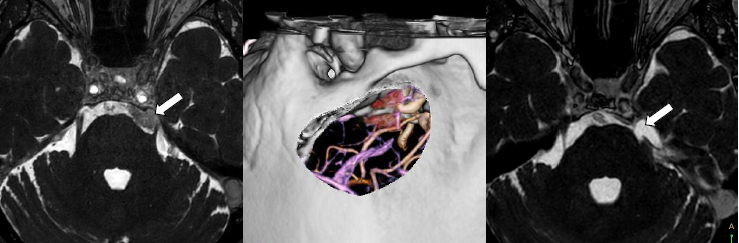

三叉神経痛で発症した錐体斜台部髄膜腫です。

術前シミュレーションで骨削除範囲を決めて手術を行いました。